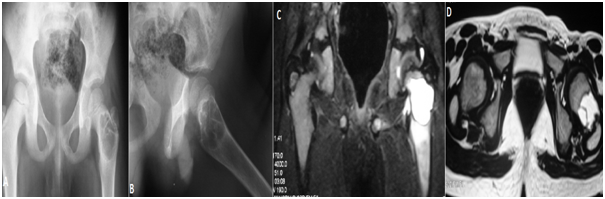

Figure 1 Juxta articular tibial aneurismal bone cyst close to proximal phuses in 3 years old girl A. Plain X-ray AP and lateral B,C: MRI of the same case sagittal and axial cuts shows septum and how the cyst is close to physes.

Figure 2 Juxta articular tibial aneurismal bone cyst close to proximal phuses in 3 years old girl A. Plain X-ray AP and lateral B,C: MRI of the same case sagittal and axial cuts shows septum and how the cyst is close to physes.

Figure 4 A, B: Plain X-ray with proximal femoral Aneurysmal bone cyst AP and Lat. C,D: MRI pelvis with huge cyst close to the physes.